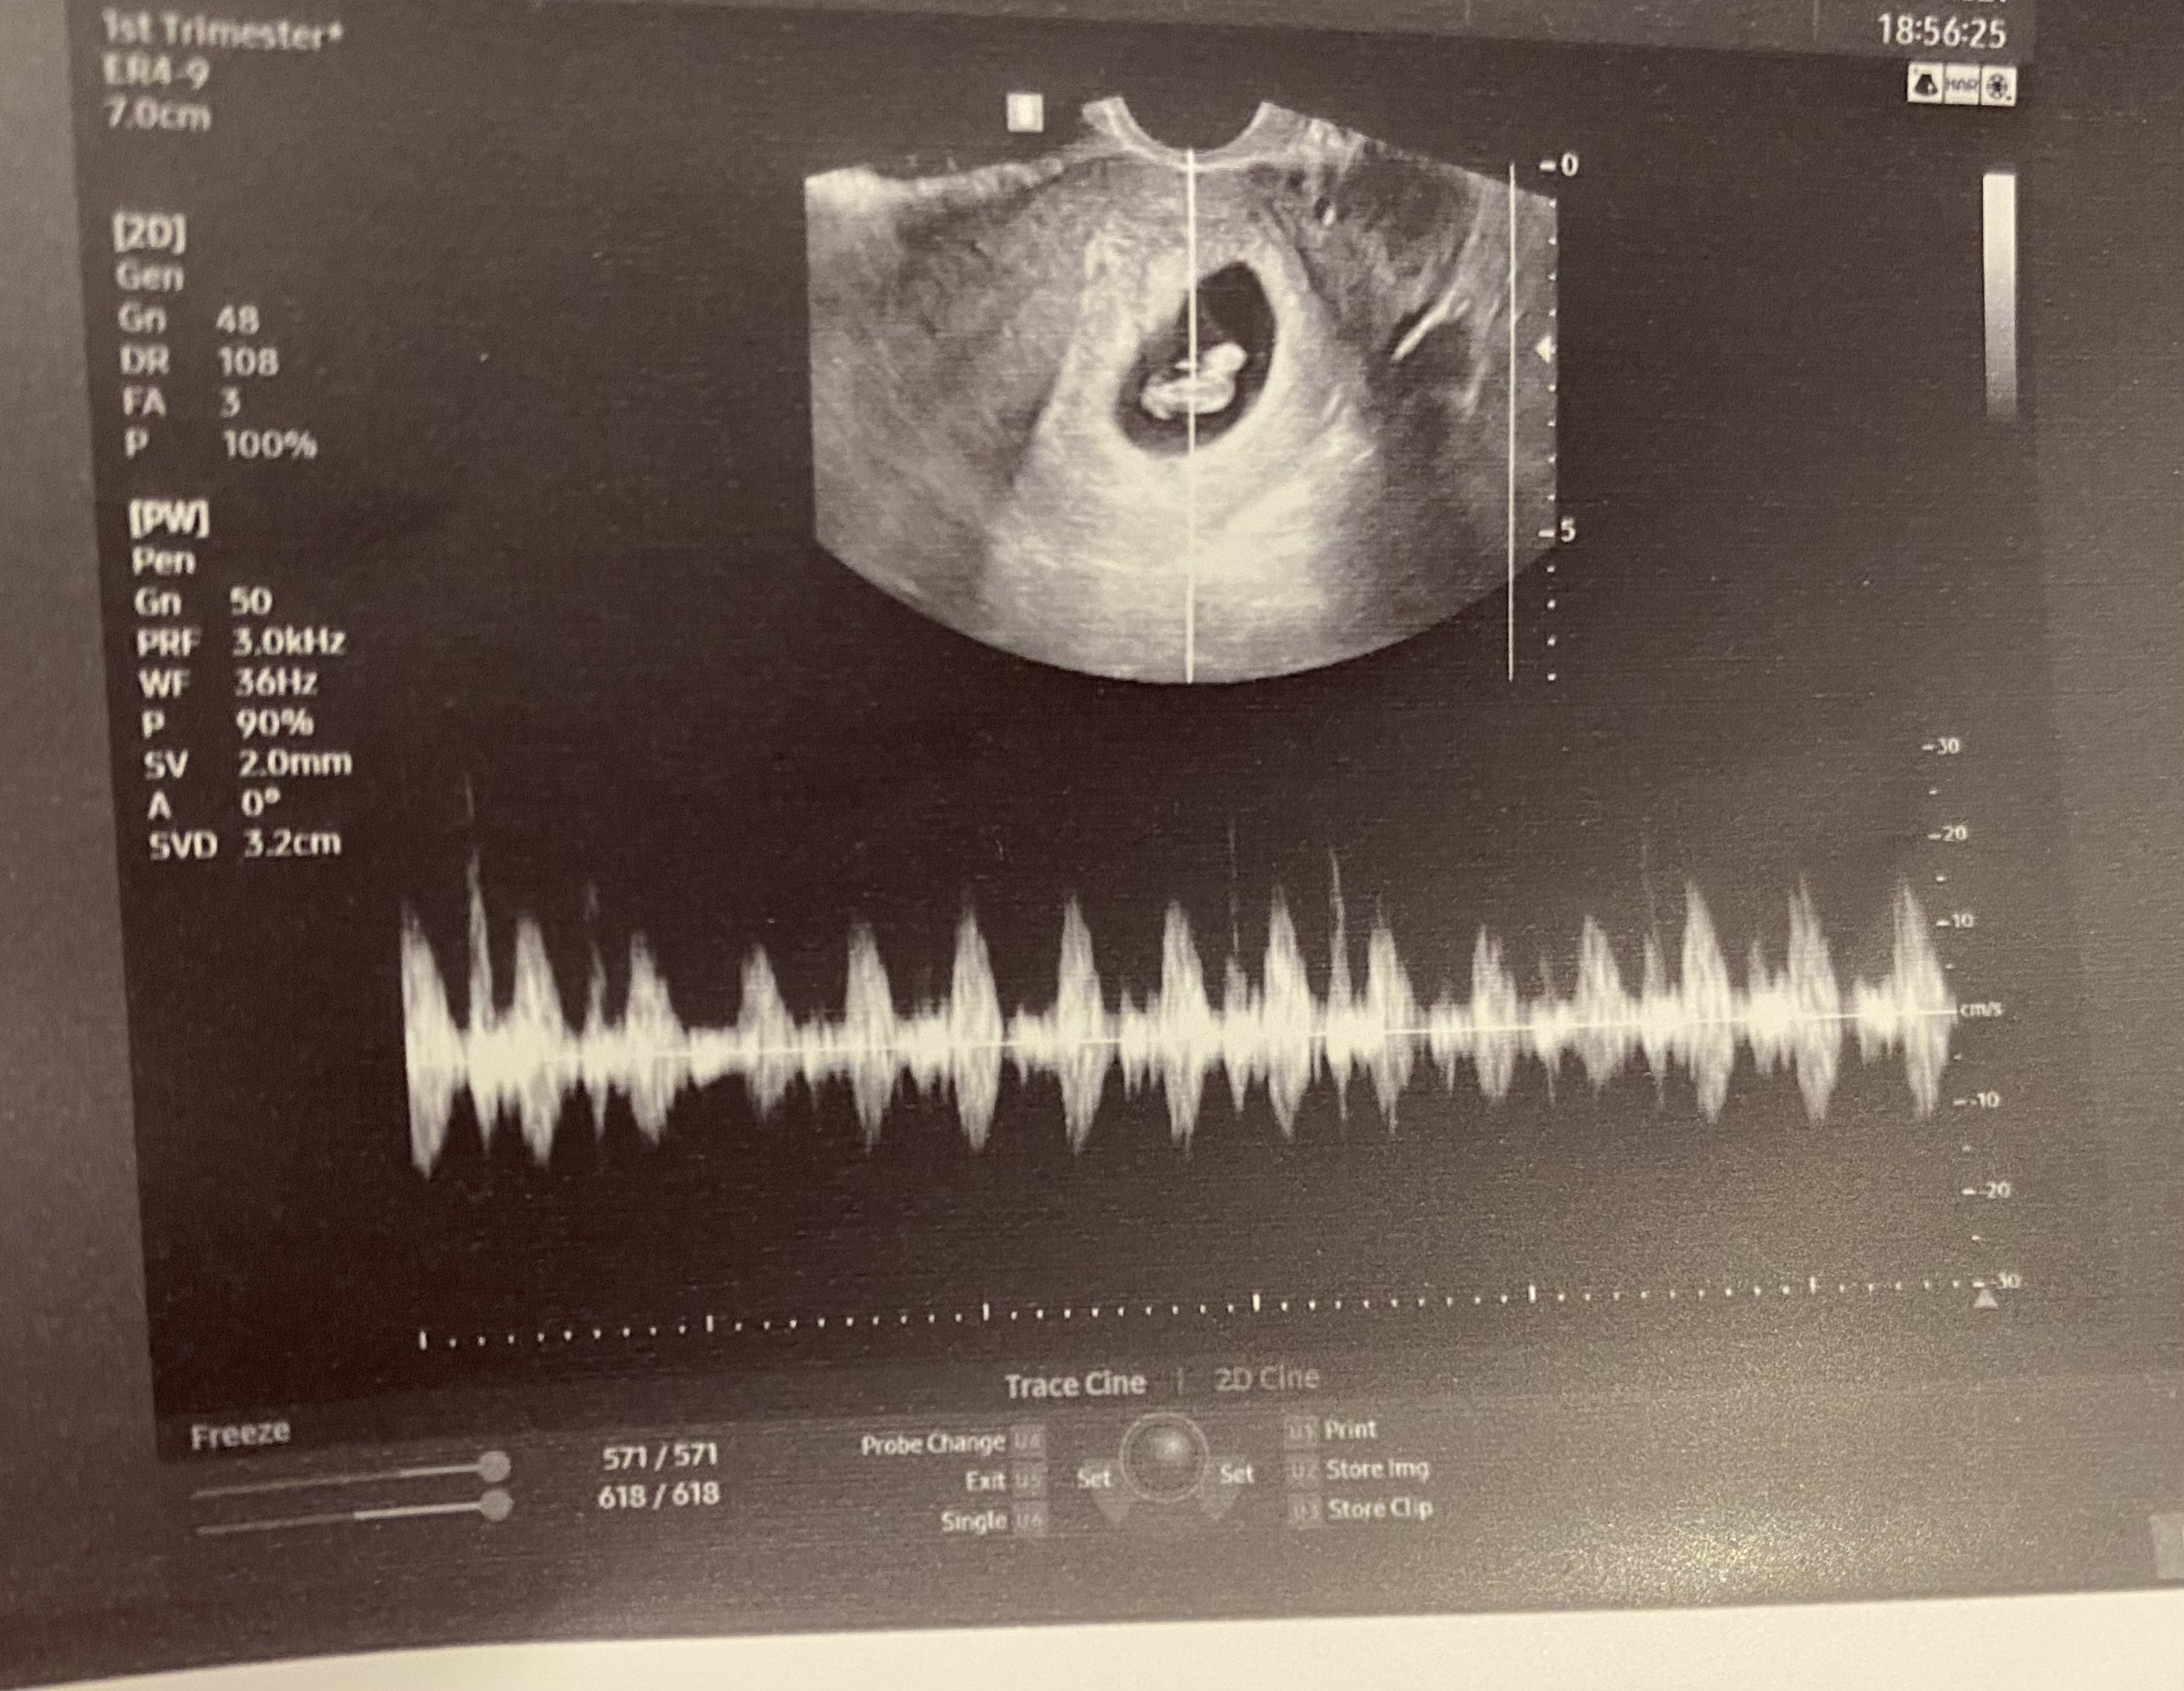

Dziewczyny dzidzi jest! Serduszko bije !❤️Wszytsko jest dobrze !:) uffff;) dostałam zalecenia badań i będę robić !:) dziękuje Wam za wsparcie, jesteście nieocenione !

tylko nie wiem gdzie tu tętno jest hmmm

• 65829535-0CA7-42FB-81F0-2D9377CB7081.jpeg

65829535-0CA7-42FB-81F0-2D9377CB7081.jpeg

1,3 MB · Wyświetleń: 120